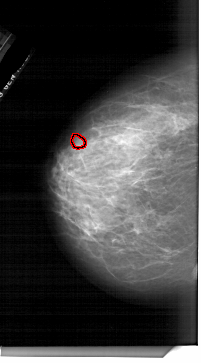

A_1761_1.LEFT_MLO

LEFT_MLO LINES 6271 PIXELS_PER_LINE 3886 BITS_PER_PIXEL 12 RESOLUTION 43.5 OVERLAY

FILE: A_1761_1.LEFT_MLO.OVERLAY

TOTAL_ABNORMALITIES 1

ABNORMALITY 1

LESION_TYPE MASS SHAPE OVAL MARGINS ILL_DEFINED

ASSESSMENT 4

SUBTLETY 3

PATHOLOGY BENIGN

TOTAL_OUTLINES 1

BOUNDARY